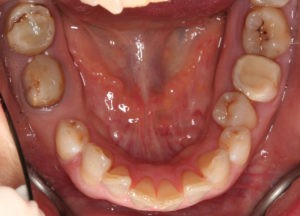

Пациентка, 43 года обратилась в клинику с жалобами на наличие промежутков между зубами, измененный наклон передних зубов верхней челюсти, появившейся за последнее время. Также пациентку беспокоил изменившийся профиль лица.

Для предварительной подготовки были привлечены пародонтолог и ортопед, поскольку отсутствие нескольких зубов, заболевание пародонта и дефекты твердых тканей зубов сопутствовали основной патологии. Проведены пародонтологические процедуры, вылечен кариес и его осложнения, изготовлены временные коронки для зубов с большим разрушением. На фото — временные коронки на боковых зубах.